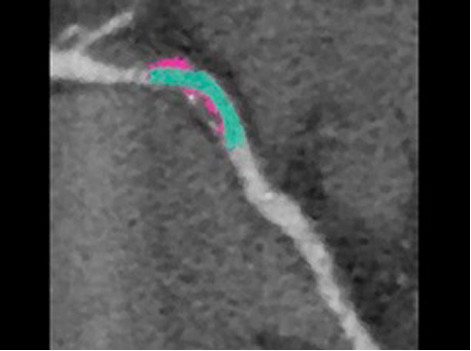

Vivid S70N and Vivid iq IntraCardiac Echo (ICE8,9) E95

ICE technology combined with CARTOSOUND™ provides exceptional image detail, strengthening real-time monitoring and guidance during procedures.  Read More